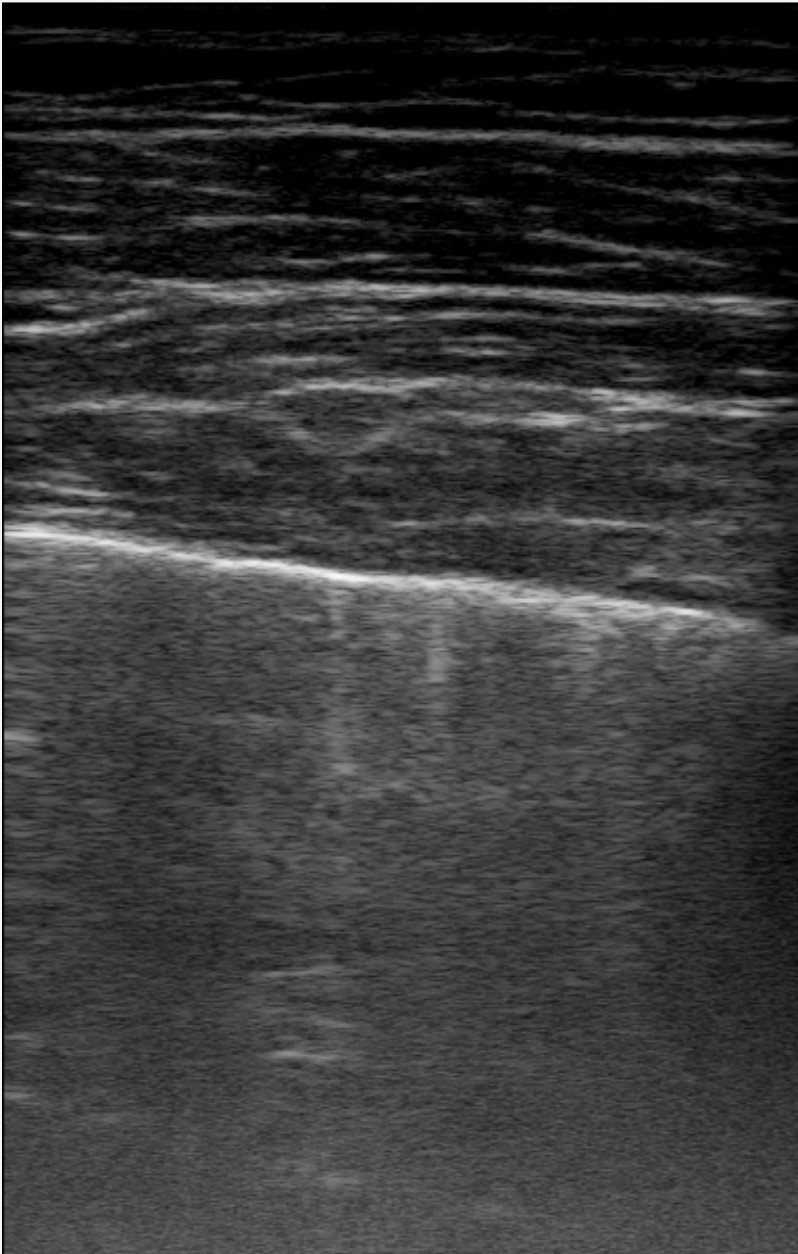

Figure 1 is an example segmentation label, thresholded by confidence to show the distribution of confidences in a single example. As the confidence threshold increases, the resulting segmentation labels get more refined. However, there may be a loss of features in the labels once the thresholds get sufficiently higher than the expert’s confidence in that feature’s appearance. For example, vertical lines disappear once the threshold becomes 40% in Figure 1. By thresholding the confidence labels this way and conducting further analysis with downstream tasks, we can gain a sense of how prominent these LUS features need to be for them to be clinically relevant.

The performance of our models in segmenting specific lung ultrasound features is represented in Figure 3. None of the models demonstrated a consistent advantage across all features, highlighting that each model possessed relative strengths and weaknesses depending on the visual characteristics of the target. For example, the model trained with 100% confidence labels performed best at segmenting features that typically appear as intensely bright, relatively isolated large areas, such as certain vertical artifacts (B-lines) and sub-A lines. These features may be easier to delineate due to their high contrast and limited overlap with surrounding structures. In contrast, models trained with lower thresholds, such as the 50% confidence model, performed relatively well on pleural features, indicating that this model is potentially better at identifying structures that are less uniformly bright or more linear and contiguous, such as the pleural line itself, which requires recognizing a specific pattern along a boundary. Across the models, there was a general tendency to struggle with thin, elongated structures like a sharp pleural line and fine sub-A lines, while performing better on features that occupy larger areas of the image or have a more amorphous appearance, such as a thickened, "fuzzy" pleura or fascia bands in the chest wall.

Figure 4 shows example segmentation outputs for the same test example shown in Figure 1. Each image represents the segmentation output of a model trained with the relevant confidence threshold. Similar to the expert labels, the segmented clinical features tend to get more refined as the confidence threshold increases. The 100% model tends to over-segment features, while the 100% model misses some features entirely, as expected.